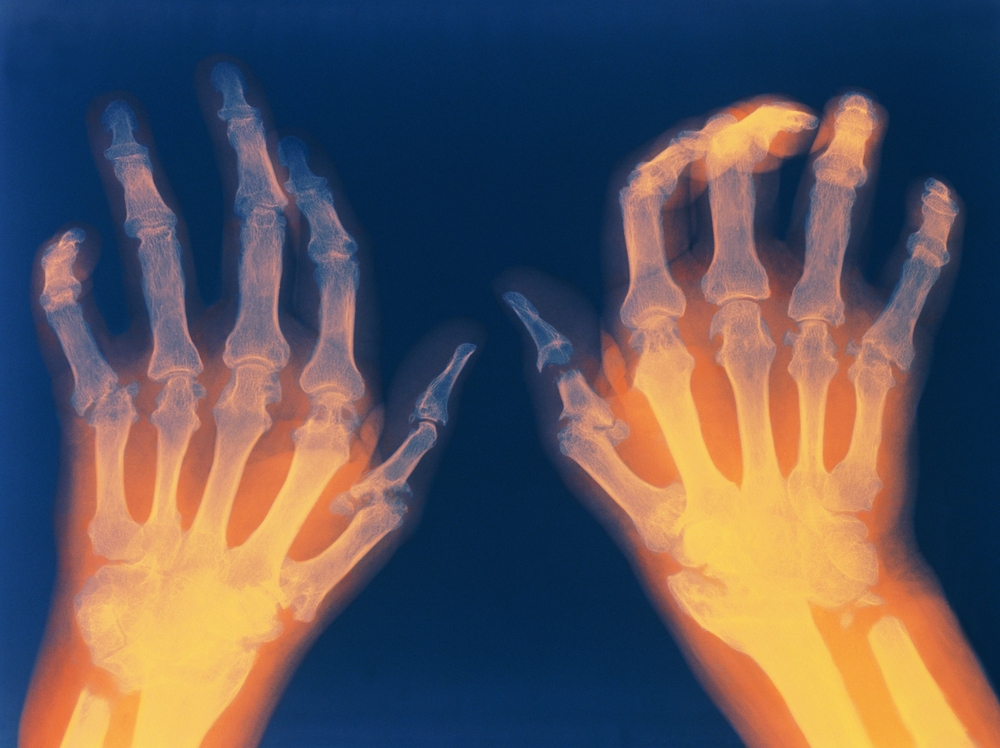

Reumatoidalne zapalenie stawów (RZS) jest to przewlekła, autoimmunologiczna choroba układu ruchu, charakteryzująca się stanami zapalnymi stawów, które prowadzą do bólu, sztywności oraz utraty sprawności. Uważa się, że czynniki genetyczne i środowiskowe, w tym styl życia, odgrywają kluczową rolę w patofizjologii reumatoidalnego zapalenia stawów. Czynniki ryzyka związane ze stylem życia, takie jak palenie tytoniu, w tym bierna ekspozycja na dym papierosowy, nieodpowiednia dieta, niedobór przeciwutleniaczy i wysokie spożycie czerwonego mięsa, mogą zwiększać ryzyko rozwoju RZS.

Podstawę leczenia stanowi włączenie leków farmakologicznych w łagodzeniu objawów reumatoidalnego zapalenia stawów (RZS) i spowalnianiu postępu choroby. Coraz więcej badań i doświadczeń klinicznych wskazuje, że równie ważnym elementem terapii jest odpowiednio dobrana dieta i suplementacja. Liczne badania wskazują, że odpowiednio zbilansowana dieta może wspierać działanie leków, łagodzić stan zapalny, poprawiać samopoczucie i wpływać na ogólną jakość życia osób z RZS. Należy jednak pamiętać, że skuteczność diety zależy od indywidualnych cech pacjenta, między innymi: jego stanu zdrowia, poziomu aktywności, masy ciała, współistniejących schorzeń oraz stylu życia. Pacjenci z RZS mają wyższe ryzyko rozwoju chorób współistniejących, takich jak otyłość, choroby układu krążenia, osteoporoza i cukrzyca, co dodatkowo komplikuje leczenie choroby.